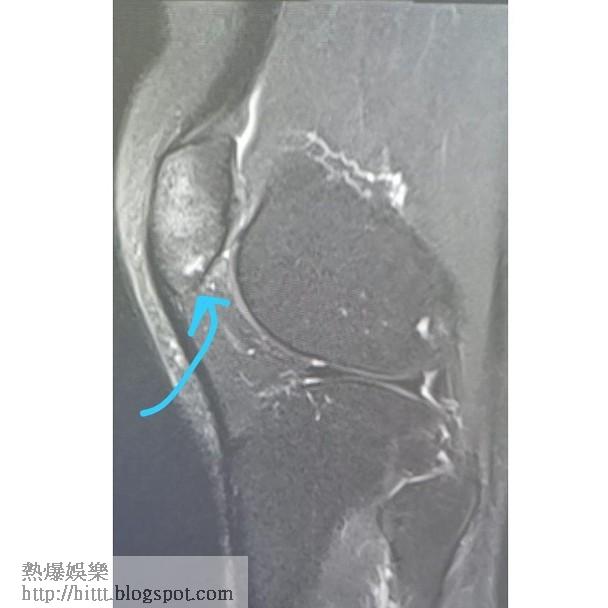

歌手林欣彤(Mag)早前放狗時,因愛犬突然失控令她失足仆落樓梯,導致手腳、下巴受傷,要靠坐輪椅出入。事後她休養僅一周便火速復工,惟今日(22日)她在社交網晒出一張X光照,自爆原來膝蓋骨裂,傷勢比想像中嚴重得多!

她發文表示:「原來我嘅膝頭哥底真係骨裂咗...唔怪得知成個月都未好番晒,可能因為我嘅忍耐能力比較強一點點...所以大家都話應該唔係骨裂嘅,如果唔係會痛到點點點,所以一直都冇照任何野,抖左一星期我就繼續照行照郁照做家務照工作,以為骨應該冇事,但真係太想做運動所以尋日先去照一照,點知...」她續指醫生提醒要多休息,暫時不能做運動及着高踭鞋,但就笑指:「輕微骨裂對我來說是小兒科!」叫大家不用擔心。